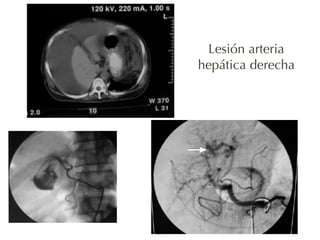

Lesión arteria

hepática derecha

82

hepática derecha y

de la vía biliar

ipsilateral